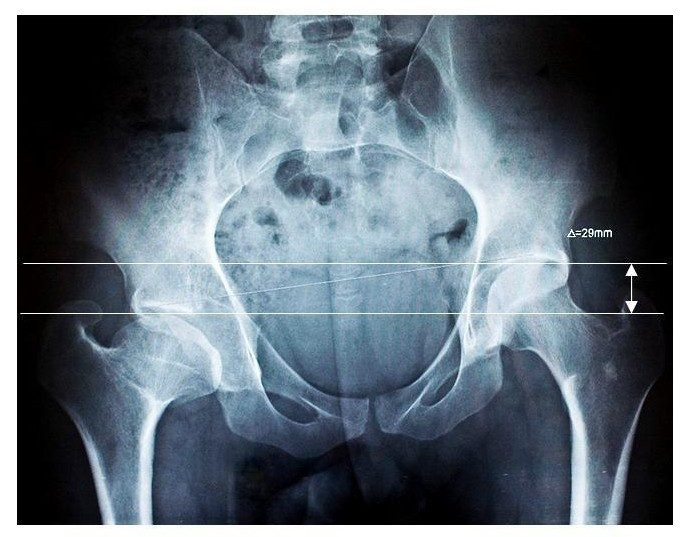

Beinlängendifferenz (BLD)